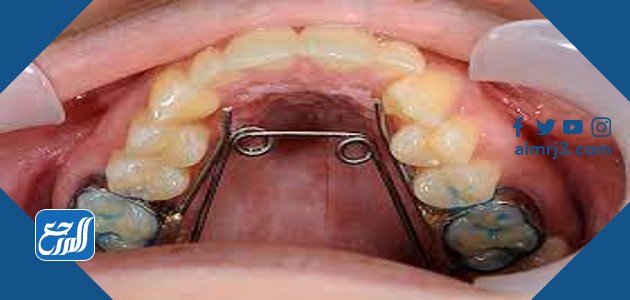

جهاز توسيع الفك العلوي هو عبارة عن جهاز معدني له مفتاح في المنتصف للتوسيع والتضيق، ويتم تركيب الجهاز في منتصف حلق المريض العلوي وتخرج منه أذرع معدنية إلى الأسنان والضروس المقابلة والتي تكون غير منتظمة الشكل وتحتاج إلى تقويم، ومع مرور الوقت يتم توسيع الجهاز بمعدل معين غالبًا ما يكون 1 ملي في كل شهر ليساعد في إعادة الأسنان إلى مواضعها الطبيعية، وفيما بعض تجارب الأشخاص الذين قاموا بتركيب الجهاز على أسنانهم العلوية:

- الجهاز رباعي المسامير ويعد من أكثر الأجهزة التي تستعمل بكثافة في علاج مشكلات الفم والأسنان.

- جهاز تمديد الفك العلوي وهو جهاز يتم تركيبه على الأسنان ليقوم بتحريك الأسنان التي نمت في المكان الخاطئ ومن ثم يعطي الفرصة للأسنان السفلية للظهور في مكانها الأصلي.

- جهاز توسيع الأسنان والذي يستخدم عندما تكون الأسنان متراكبة بعضها فوق بعض لا سيما الأسنان الأمامية فيعمل الجهاز على إعادة كل سن إلى مكانه الطبيعي.